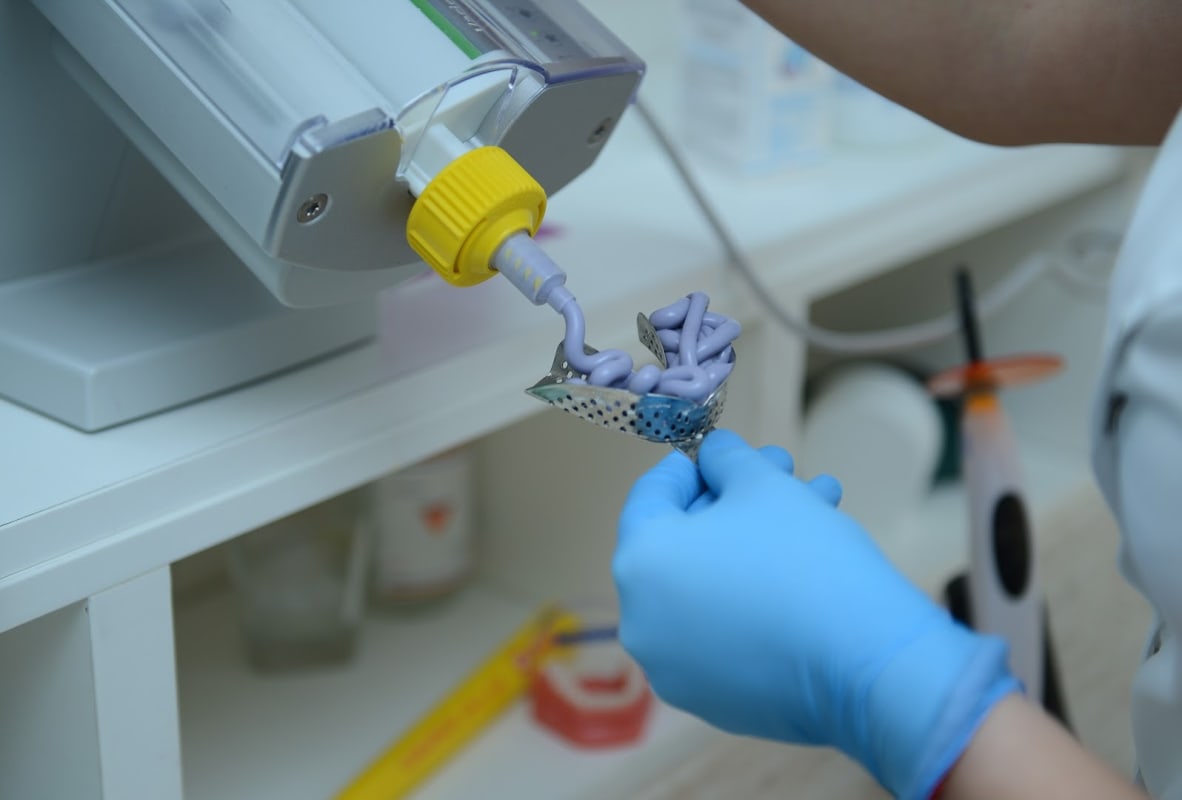

Zahnklinik mit ästhetischer Zahnmedizin, Implantaten, Veneers und Kieferorthopädie sowie Zahnmedizintourismus-Paketen und kostenlosen Beratungen.

Zecevic Dental ist eine Zahnklinik unter der Leitung von Dr. Zelko und bietet ästhetische Zahnmedizin, Endodontie, Implantologie, Veneers, Kieferorthopädie und Röntgen-Orthopan an. Die Klinik positioniert sich für Zahnmedizintourismus mit Behandlungspreisen, die 70 bis 80 Prozent unter den Sätzen in den USA, Australien und Westeuropa liegen. Kostenlose Beratungen werden angeboten. Transport und Unterkunft können als Teil von Komplettpaket-Zahnbehandlungen arrangiert werden. Öffnungszeiten: Mo–Fr 9 bis 21 Uhr, Sa 9 bis 13 Uhr, So geschlossen. Terminvereinbarung erforderlich. Karten-, Debit- und kontaktlose Zahlungen akzeptiert.